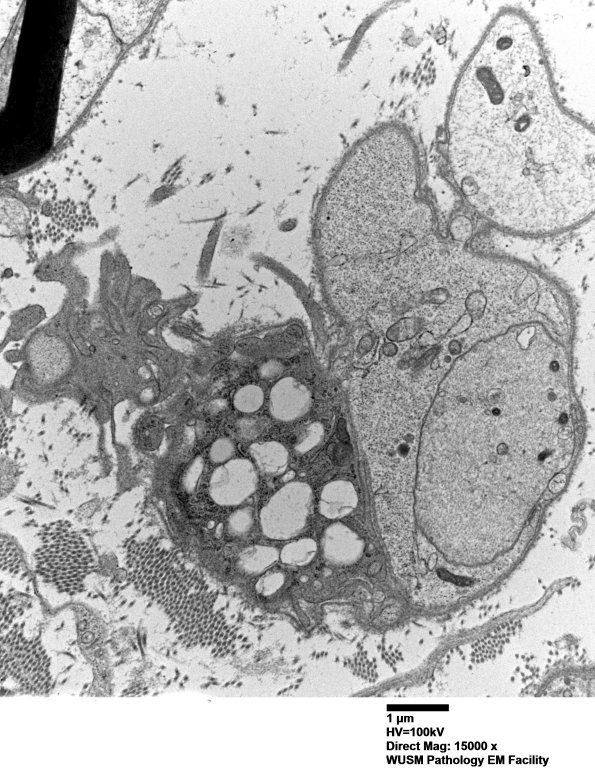

Washington University Experience | PERIPHERAL NEUROPATHY | 7B CIDP | 4F5A Case 4 Ant Interosseus nerve_033.jpg

There are numerous axons which are completely demyelinated and associated with nearby macrophages with myelin debris. (electron micrographs)